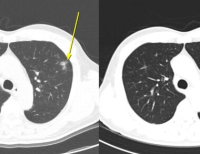

카스게비는 재발성 혈관폐쇄 위기(vaso-occlusive crises, VOCs)를 겪고 있고 12세 이상의 겸상(鎌狀)적혈구질환(sickle cell disease, SCD) 치료제로 승인받았다. 영국에서는 수혈 의존성 베타 지중해빈혈(TDT)을 앓는 12세 이상 환자의 치료제로도 승인됐으나 미국에서는 별도로 승인 신청이 이뤄져 심사 중이다. FDA 심사 기한은 내년 3월 30일까지로 정해졌다. 현재 유럽의약품청(EMA)도 카스게비를 겸상적혈구병 및 베타 지중해빈혈 치료제로 심사 중이다.

카스게비는 유전자 변형 자가 CD34+ 세포 농축액으로 구성된 제형이다. 환자의 조혈모세포(줄기세포) 및 그 전구체를 꺼내 체외에서 CRISPR/Cas9를 통해 BCL11A 유전자의 적혈구 특이적 발현 촉진자(enhancer) 영역에 근접해 이를 파괴하는 유전자편집 과정을 거친 다음 다시 체내로 주입하는 유전자 교정 치료제다.

BCL11A는 태아 헤모글로빈 성분 중 γ-글로빈의 발현을 억제하는 전사인자다. 카스게비는 BCL11A 유전자를 Cas9으로 제거해 태아 헤모글로빈의 발현을 촉진하는 전략으로 환자의 β-글로빈 기능을 대체하는 치료제다.

연구진들은 크리스퍼 유전자 가위를 이용해 출생 이후 감마를 억제하는 물질을 만드는 BCL11A 유전자를 제거했다. 그랬더니 환자의 체내에서 다시 감마 헤모글로빈이 만들어지기 시작했고, 이들이 제 기능을 못 하는 베타 헤모글로빈을 대신해 산소 운반을 담당하면서 증상이 개선됐다.

‘CLIMB-121’ 임상시험 결과, 카스게비로 치료받은 환자의 90% 이상에서 1년 이상 해당 질환의 주요 증상이 나타나지 않은 채 건강을 유지했다. 유전자치료의 특성상 단 한 번의 치료로 끝났다.